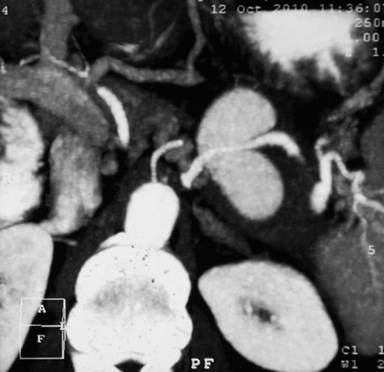

A hematological work-up, including hemoglobin and liver function tests, was normal. A contrast enhanced computed tomography scan (Figures 1 and 2) revealed features of chronic pancreatitis with multiple foci of calcifications in the pancreatic duct and parenchyma involving the body and tail. The pancreatic duct was not significantly dilated. There was a large pseudoaneurysm measuring 7x4 cm in size in the splenic artery. In addition, there was a pseudocyst measuring 6x4 cm in size in the omentum, separate from the pancreas.

Figure 2. CT scan coronal reconstruction showing a giant pseudoaneurysm of the splenic artery with the artery passing through the pseudoaneurysm. |